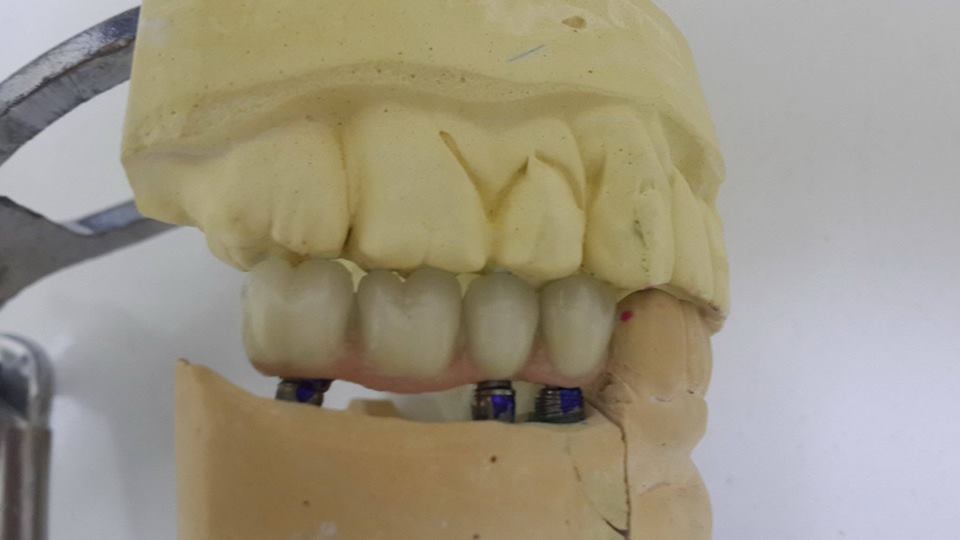

An example of complete rehabilitation of the oral cavity. Treatment included the removal of the old prosthesis, treatment of paradontitis, removal of a large cyst, implantation, clasp prosthesis.